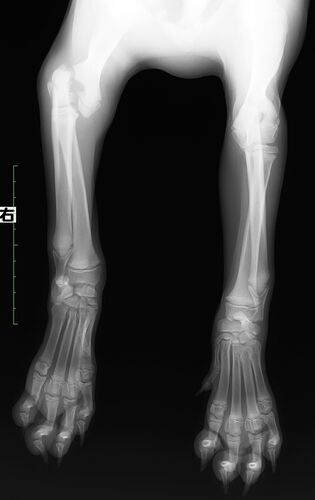

4ヶ月ゴールデンレトリバーの骨折

症例は4ヶ月、未避妊のゴールデンレトリバー。階段から落ちてから、前足の破行を主訴として来院されました。レントゲンを撮影すると、右上腕骨顆間骨折を起こしていました。 成長期の骨格には、骨の両端にある成長板という場所から軟骨細胞が骨化して、骨が…